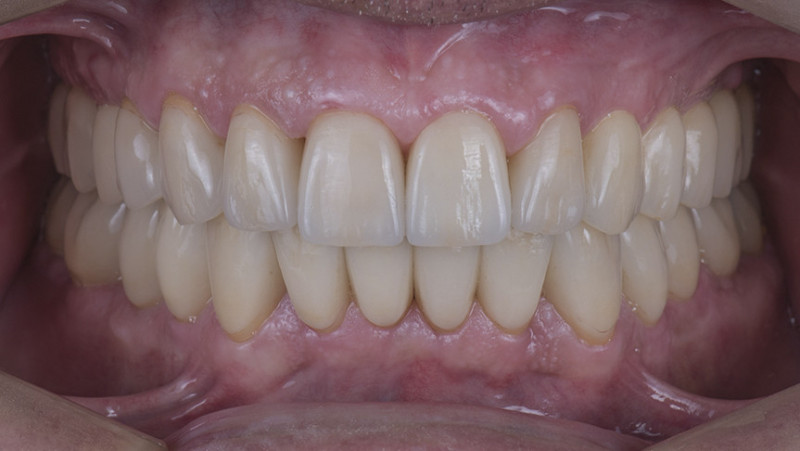

Установка коронки на зуб

Провели швейцарскую профгигиену. Перелечили зубы с несостоятельными пломбами и воспалениями. Удалили 7 зубов на верхней и нижней челюсти с одномоментной имплантацией 9 имплантатами, костной пластикой и пластикой десны. После приживления имплантатов установили временные коронки. Изготовили и установили абатменты Procera и 28 единиц керамических коронок EMAX.